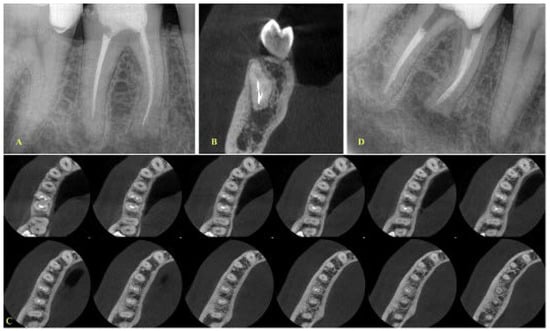

- In cases where the canals were merging, then a final treatment plan of leaving the fragment in situ was set, irrespective of the presence or absence of lesions (Figure 3 and Figure 4). The only occasion that would induce a modification to this treatment plan (i.e., leave the fragment in situ) was to conclude, after CBCT assessment and evaluation of canal curvature, that the removal of the fragment located at the middle level of the root would not be of a high difficulty degree procedure (Figure 5).